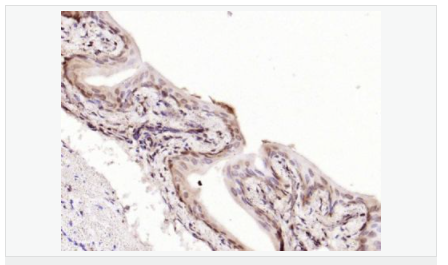

image.png